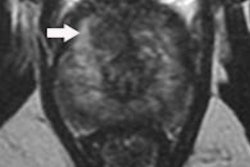

SV volumes were measured manually. To clarify if the statistically significant volume differences had a meaningful effect on diagnostic interpretability, two readers were asked to judge the interpretability of the SVs. Two radiologists who were blinded to group assignment and patient characteristics scored the right and left SVs separately to determine diagnostic interpretability, using a three-point scale: A score of 1 denoted the SVs were not dilated and the score was nondiagnostic; a score of 2 indicated the SVs were not dilated but the score was diagnostic; and a score of 3 denoted the SVs were dilated and the score was diagnostic.

The right, left, and total SV volumes for group 1 were 3.1 mL, 2.9 mL, and 6.0 mL, respectively, whereas those for group 2 were 4.7 mL, 4.1 mL, and 8.8 mL, respectively (p = 0.011). The mean interpretability scores for group 1 and group 2 were 2.0 and 2.5, respectively. For group 1, reader 1 and reader 2 assigned a nondiagnostic score for 10 and 13 patients (23.8% to 31%), respectively, whereas for group 2, they assigned a nondiagnostic score for two and five patients (4.75% to 11.9%), respectively (p = 0.01, for reader 1; and p = 0.03, for reader 2).